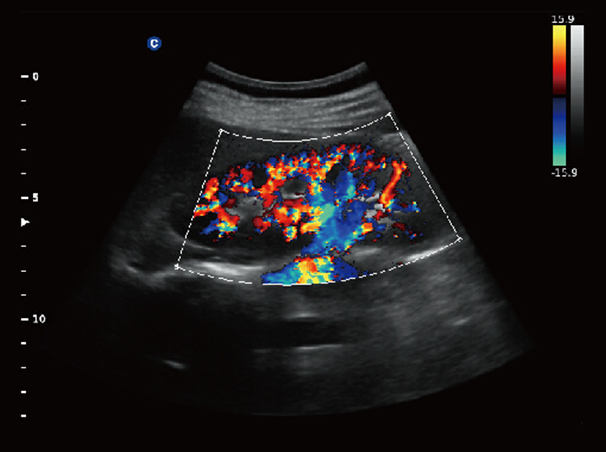

Chison Qbit 3 Color Doppler Digital Ultrasound Machine

Chison Qbit 3 A Slim Console Color Doppler System, Offers Ideal Patient Care With Its Easy Mobility, Smart Features, Significant Performance And Streamlined Workflow, To Strengthen The Clinical Confidence And Speed The Diagnostic Decision.

Chison QBit-3 Ultrasound Machine System, Offers Ideal Patient Care With Its Easy Mobility, Smart Features, Significant Performance And Streamlined Workflow, To Strengthen The Clinical Confidence And Speed The Diagnostic Decision.